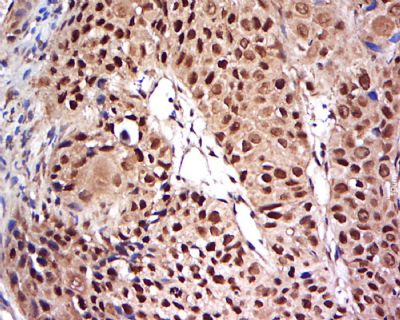

细胞核因子/k基因结合核因子抗体

目录号:bs-20159R

商品规格:50ul